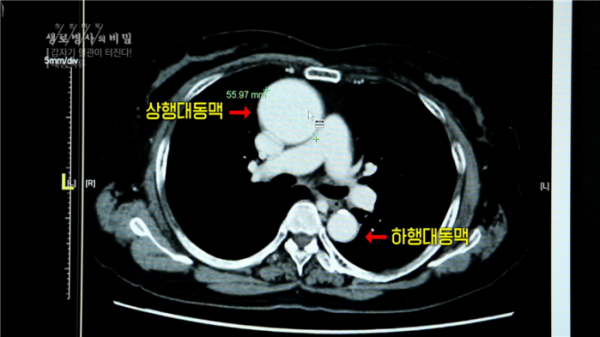

23일 방송되는 KBS1 '생로병사의 비밀'에서는 터지기 전 증상이 없지만, 갑자기 터지면 사망률이 급격히 올라가는 대동맥류에 대해 방송한다.

우리 몸의 가장 큰 혈관인 대동맥이 풍선처럼 부풀어 오르는 대동맥류는 한 번 부풀어 올라 파열되면 생명을 위협하는 무서운 질환이다.

해마다 흉부·복부대동맥류 환자는 2014년 21,102명에서 2018년 29,137명으로 꾸준히 늘어가고 있다. 뇌혈관이 부풀어 오르는 뇌동맥류 또한 5년 새 2배가량 환자가 증가하고 있다. 문제는 이 대동맥류가 ‘몸속 시한폭탄’이라고 불리기도 하는 위험한 질환이지만 터지기 전까지는 대부분 뚜렷한 증상이 없어 잘 모른다는 것이다.